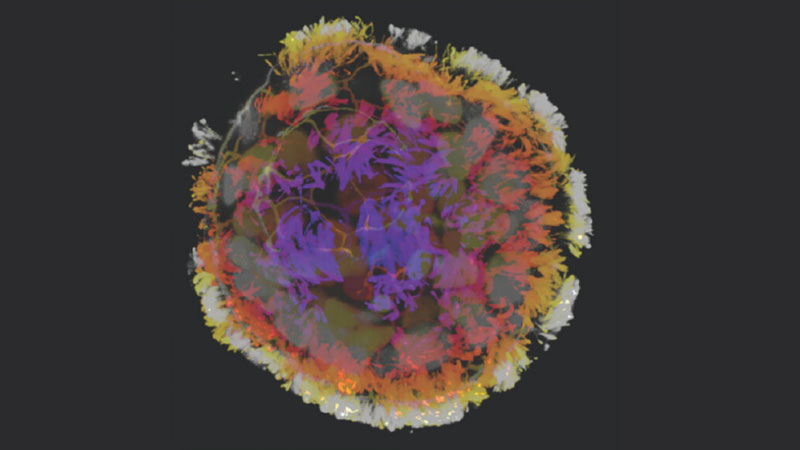

Um antropobô feito de várias células pulmonares humanas modificadas. Fonte da imagem: Gumuskaya et al, Ciência Avançada

Cada robô antropomórfico consiste em várias células pulmonares humanas. Essas células são cultivadas separadamente em um ambiente especial e depois se agrupam em grupos. As células pulmonares possuem cílios, que são capazes de movimentos caóticos para realizar uma série de funções biológicas. Os cientistas tiveram que inventar tal meio para que os cílios crescessem fora das células ao longo de toda a sua superfície. Quando as células se reuniram em uma estrutura multicelular, os cílios as cobriram completamente. Tal célula poderia mover-se em qualquer direção.

Os cientistas identificaram dois tipos de células: algumas tinham formato mais esférico, enquanto outras eram elípticas. Descobriu-se que os aglomerados esféricos marcavam principalmente o ritmo. Os movimentos dos cílios na superfície esférica compensavam-se entre si. Os corpos elípticos revelaram-se capazes de movimento. A trajetória do movimento dependia da densidade dos cílios em uma determinada área do coágulo, mas era predominantemente um movimento circular.